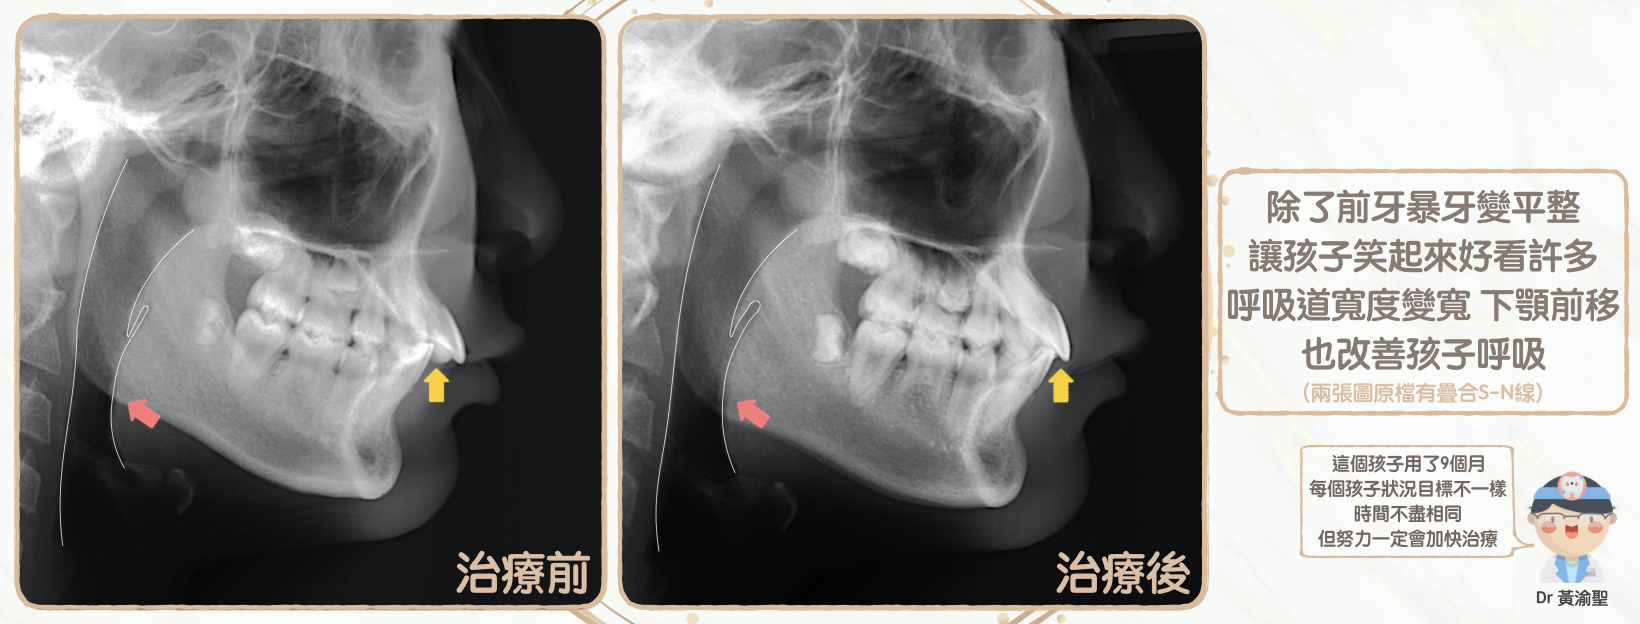

小綺與爸爸媽媽非常滿意暴牙改善

而且深咬也變淺了

經過數據量測

小綺的下顎骨前移

呼吸道也更寬闊了

都是非常棒的改善